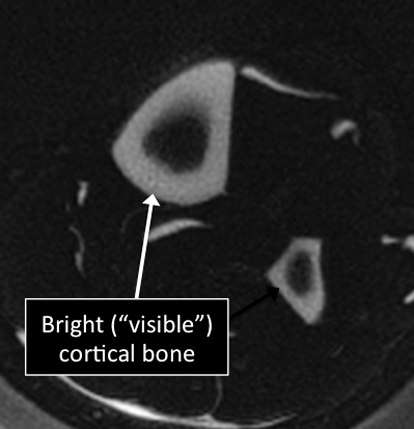

Leg MRI examinations showing normal (top) and abnormal (bottom) cortical bone.

Why Translational MRI of the bone?

- In the bone, as in many other tissues of the body there are certain structures that can’t be seen (they look black or dark) with the standard MRI.

- There are new “software” programs that allow us to see structures with different contrast (bright versus dark).

- In the bone these “invisible” or dark structures include cortical bone, subchondral bone plate and vertebral endplate.

Leg MRI examinations using the standard MRI techniques (top) and translational MRI techniques (bottom).